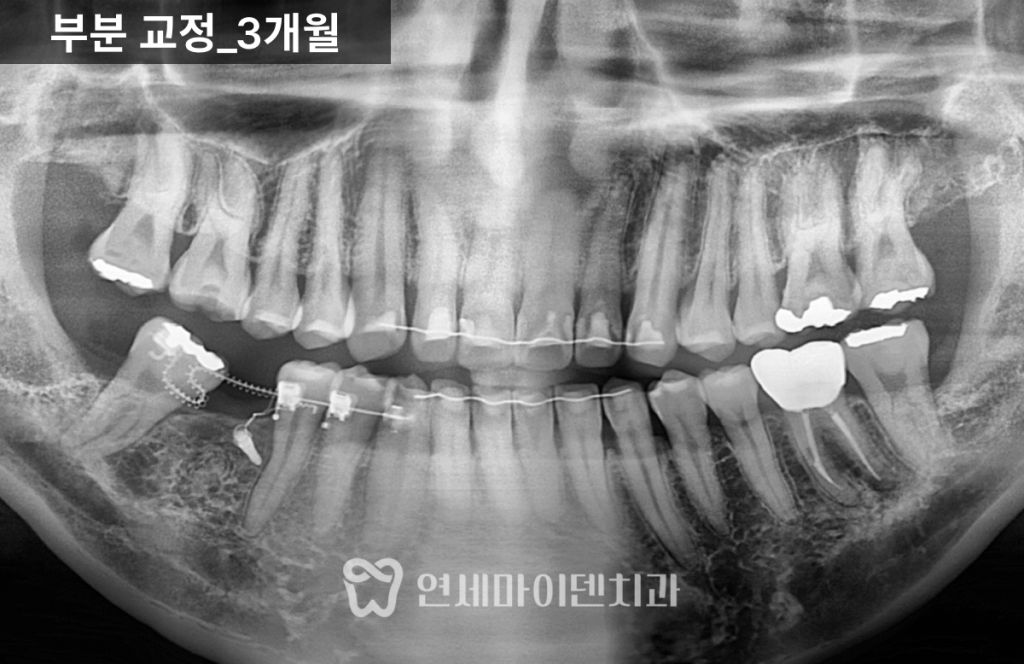

부분교정 3개월 경과

교정 초반에는 부드럽고 얇은 와이어를 사용해

치열의 기본 정렬을 유도했습니다.

이후에는 쓰러진 7번 어금니를 세우기 위해

특수 제작된 접은 철사와 코일 스프링을 병행했습니다.

일반적인 일자 철사 대신,

치아를 원하는 방향으로 정교하게 이동시키기 위해

맞춤형 와이어를 적용했습니다.

3개월 경과 시점에서는

점점 어금니가 세워지며, 임플란트 공간이

서서히 확보되는 변화가 확인되었습니다.